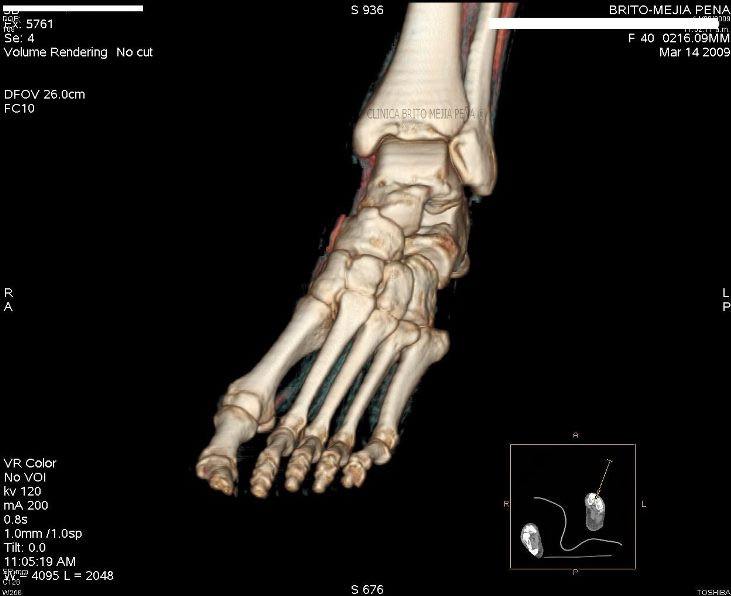

Pié normal anterior